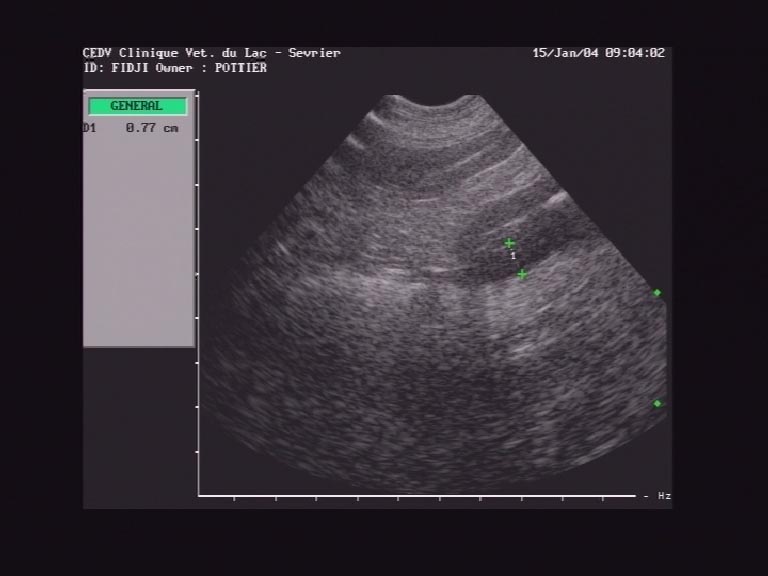

Image en coupe longitudinale d'une masse evoquant une tumeur digestive

L'examen échographique BD est pratiquée. la partie antérieure droite de l'abdomen est explorée. Dans un premier temps, une image supecte ressemblant à une anse digestive dont la paroi est infiltrée (epaississement à 8 mm) est mis en évidence (photo 1). Puis la masse palpable est analysée et présente plusieurs lobes d'echogénicité homogène, avec une forte vascularisation analysée au doppler couleur (photo 2) et au doppler continu. Cette dernière structure peut s'interpréter comme un noeud lympatique réactionnel. Diverses biopsies sont réalisées sur l'anse digestive et le NL.